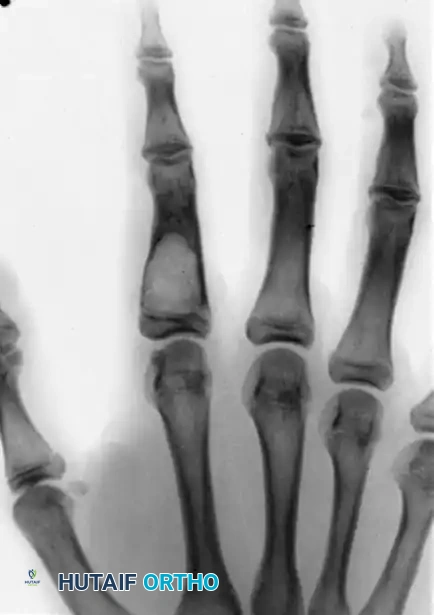

Intraoperative/Postoperative imaging demonstrating a partial-thickness fibular graft interposed after the complete excision of the osteoblastoma. The epiphyseal plate and subchondral cortex have been meticulously preserved.

Long-term follow-up (15 months post-operation) showing complete remodeling of the graft. There is no evidence of tumor recurrence, and the growth plate and carpometacarpal joint have been successfully maintained.

- Standard Treatment: For well-contained lesions, aggressive intralesional curettage combined with high-speed burring and bone grafting is the standard of care.

- Aggressive/Recurrent Lesions: Osteoblastomas can be locally aggressive. If the lesion has destroyed significant cortical bone or recurred following primary curettage, en bloc excision is required.

- Interpositional Grafting: Following en bloc resection of a metacarpal or phalanx, structural integrity must be restored. A partial-thickness or full-thickness structural autograft (such as a fibular strut graft or iliac crest graft) is interposed.